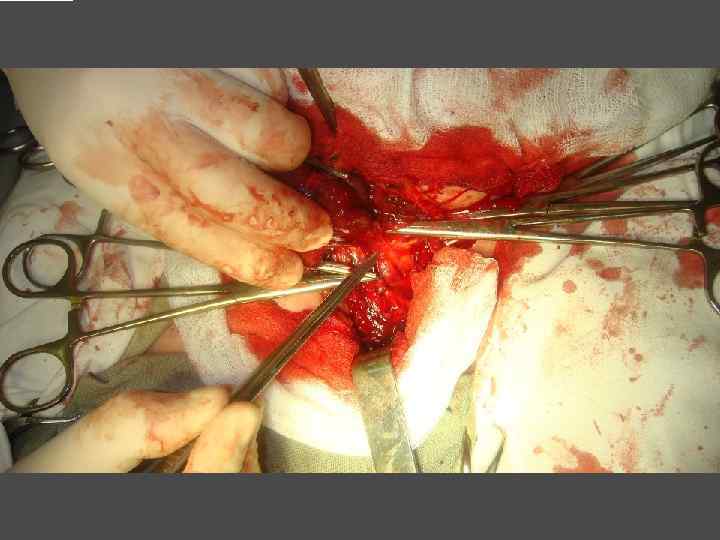

ХИРУРГИЧЕСКОЕ ЛЕЧЕНИЕ ЗОБА

ХИРУРГИЧЕСКОЕ ЛЕЧЕНИЕ ЗОБА

ОСЛОЖНЕНИЯ ХИРУРГИЧЕСКОГО ЛЕЧЕНИЯ ►Поражение возвратного нерва, приводящее к параличу голосовой связки на стороне поражения, как следствие – изменение тембра голоса, сужение голосовой щели, затруднение дыхания. ► Кровотечение. ►Тиреотоксический криз. ► Гипопаратиреоз. ► Рецидив тиреотоксикоза. ► Формирование порочного рубца.